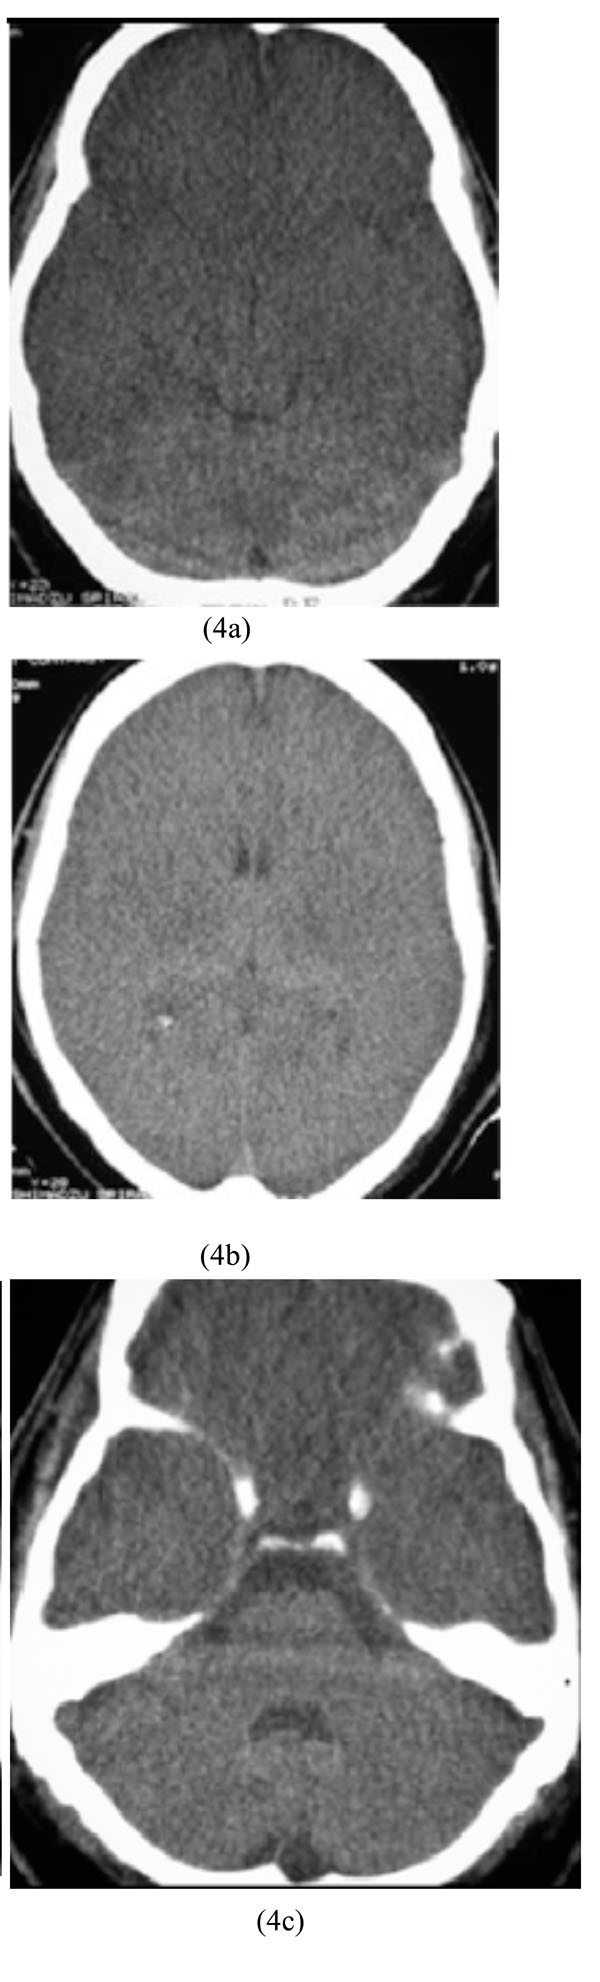

A 19-year-old man was referred to our hospital 30 hours after accidental methanol ingestion instead of ethanol. He was comatose but his family said he had reported blurred vision before becoming unconscious. Laboratory data showed severe metabolic acidosis and normal blood sugar. Ophthalmologic examination revealed papillary edema and optic disc hyperemia. Brain CT scan study before hemodialysis demonstrated bilateral basal ganglia and external capsule hypodensities with hemorrhagic focus in left side. Parasagital hypodensity was also observed (Figs. 5a-5c).

Bilateral basal ganglia and external capsule hypodensities with hemorrhagic focus in the left side along with parasagital hypodensity after accidental methanol ingestion.